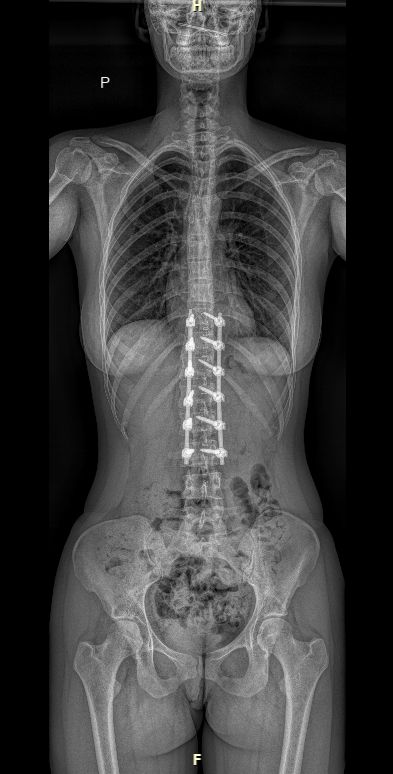

RTG celé páteře (EOS)

Jako první zobrazovací metodu obvykle provádíme RTG, případně EOS. Poskytuje nám obraz páteře v předozadní a boční rovině a umožňuje měřit stupeň zakřivení. RTG provádíme pravidelně na každé kontrole k posouzení vývoje křivky.

Kdy kontrola?

Kontroly probíhají v 6 týdnech od operace, ve 3 měsících, poté v 6 a 12 měsících a následně jednou za rok až do dospělosti. V případě obtíží je samozřejmostí kontrola kdykoliv mimo toto schéma. Na první dvě kontroly přiváží pacienta sanita (poukaz dostává od nás při odchodu z nemocnice a při ambulantní návštěvě). Na kontrolách provádíme RTG, EOS nebo CT (dle indikace lékaře) k posouzení hojení kostní dézy a stability implantátu.